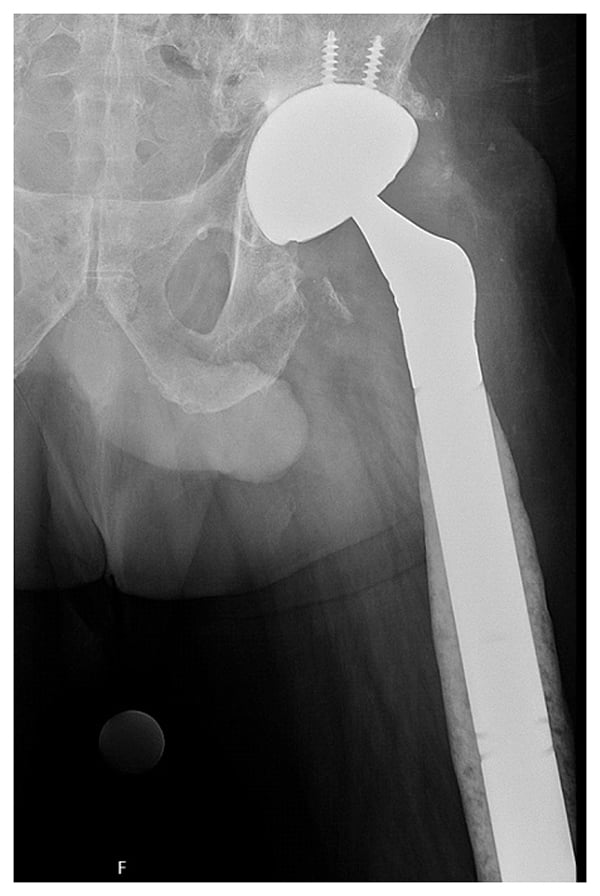

Assessment found a 4-in. leg length discrepancy, limited hip flexion to 60°, and pain and an audible clunk. Radiographs showed a revision construct with a multi-hole acetabular component fixed with multiple screws and a modular tapered stem with cerclage wires that had subsided (Fig. 1). Notably evident was a proximal femur fracture, joint dislocation, and an aggressive periosteal reaction along the diaphysis and distal metaphysis of the femur, which raised concerns for underlying osteomyelitis. With regular monitoring, antibiotic and antifungal therapies were stopped for 2 weeks, and hip aspiration was positive for Corynebacterium and Candida albicans. Due to the polymicrobial culture results and involvement of most of the femur, an explant of the revision hip replacement, resection of the distal femur, and insertion of a total femoral replacement spacer were planned.

Figure 1

Figure 1: Preoperative X-ray shows a revision arthroplasty construct most notably with catastrophic subsidence of the femoral component and evident periosteal reaction along the distal femur.